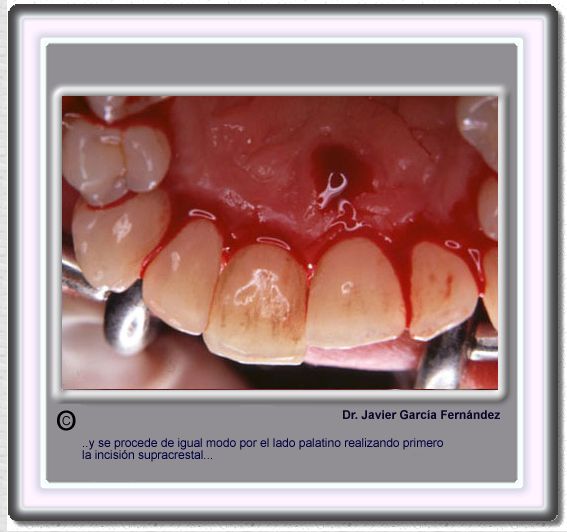

image52